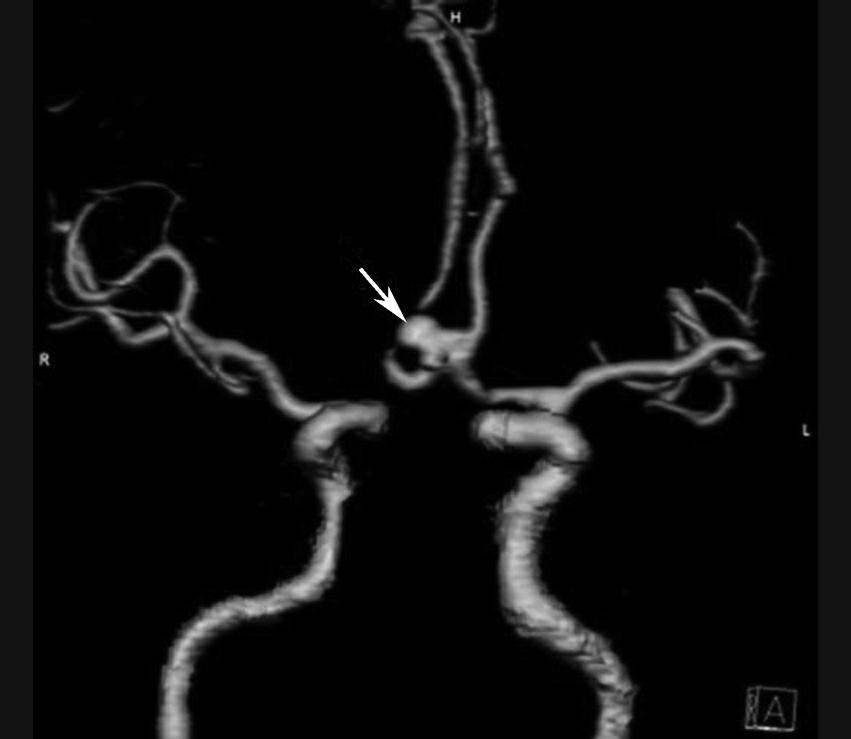

图1-2-111 前交通动脉瘤

CTA示前交通囊状动脉瘤,瘤颈较宽